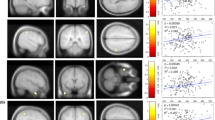

We used Stata version 14.0 for all analyses. Linear mixed modelling was used to examine the associations between each of the ETDRS regions and the brain outcome of interest adjusting for age, sex and T2D. Models of cognitive outcomes included additional adjustment for education. Twin number was entered as a random effect, so that the model allowed partitioning of within-pair and between-pair variance. To reduce the risk of false positives from multiple comparisons (right and left eye segments compared with three cognitive and six brain structural outcomes i.e., 18 independent tests of association), we used Bonferroni correction (0.05/18 = p < 0.002) across each of the cognitive and imaging modalities. Figure 1 presents a work design scheme summarizing the overall analytical approach with examples of the retinal and brain measurements.

We explored the associations of the individual retinal sublayer thickness measures with cognitive function and brain MRI measures, by ETDRS segments, corrected for multiple comparisons, adjusted for age, sex and T2D (Supplementary Tables 4–11). The positive associations between each retinal layer by ETDRS segment are summarized in Fig. 2.

Retinal nerve fibre layer thickness per se was not associated with cognitive or MRI measures (Supplementary Table 4), but ganglion cell layer thickness was positively associated with memory (segment 8, right eye), speed (segment 6, left eye), and strongly in both eyes with gray matter volume (all p < 0.002) (Supplementary Table 5). In both eyes, ganglion cell was also associated with altered mean diffusivity (segment 6, right eye and segment 4, left eye). In secondary analyses, we also found that ganglion cell layer thickness in both eyes and in many segments was strongly positively associated with regional cerebral blood flow, particularly in the insula and temporal lobes (Table 2). We found a limited number of associations between synaptic layers (inner plexiform and outer plexiform) and brain measures (Supplementary Tables 6 and 8). We found associations between inner nuclear layer thickness (Supplementary Table 7) and memory (segments 1 and 5 left eye), speed (segment 2, left eye), attention (segment 3, both eyes, segment 5 left eye), gray matter (segment 2, left eye), total cerebral blood flow (segment 3, left eye). There were associations between outer nuclear layer thickness (Supplementary Table 9) and attention (segment 6, left eye) and cerebral microbleeds (segment 1, both eyes). We found associations between retinal pigment epithelium layer thickness (Supplementary Table 10) and speed (segments 2 and 6 right eye and segment 5 left eye) and attention (segments 4 and 5 right eye). Total retinal thickness was not associated with cognitive scores but was positively associated with greater gray matter volume (segment 6, both eyes), and greater total cerebral blood flow (segment 4, 5, right eye) (Supplementary Table 11).